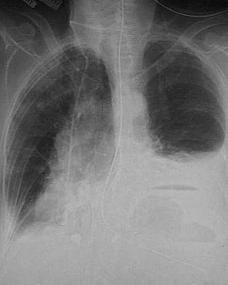

其中最常見的原因是結核性胸膜炎,而且多數情況下並不一定合併活動性肺結核。其他原因還有癌性胸水、寄生蟲引起的胸水、炎症引起的胸水等等。胸膜腔正常情況下是一個閉合的、負壓的潛在腔體,其中只有少量潤滑性液體。胸腔積液時,直接影響到肺的呼吸功能,造成胸悶氣短、心跳加速等症狀;積液吸收後,積液中的蛋白質會附著在胸膜腔內,造成朐膜粘連,長期影響肺功能。所以如果積液量較大,一般會採取抽胸水的辦法,加上抗結核病藥物、激素等,避免這一問題。